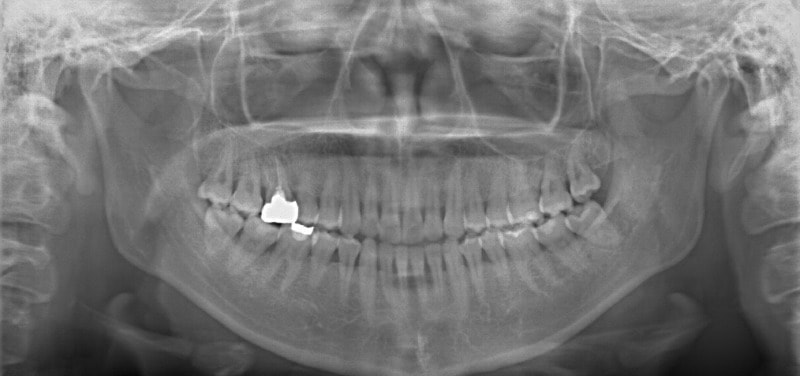

検査時パノラマレントゲン

全体の歯根のパラレリング(平行性)は悪い状態ではありません。顎関節の変形などはありません。鼻閉もありません。

成人の反対咬合なので、少し顎関節にダメージはありますが、重症ではありません。CO(中心咬合位)の位置には問題があります。CO-CRのズレが存在しますので、顎関節には負担がかかっています。